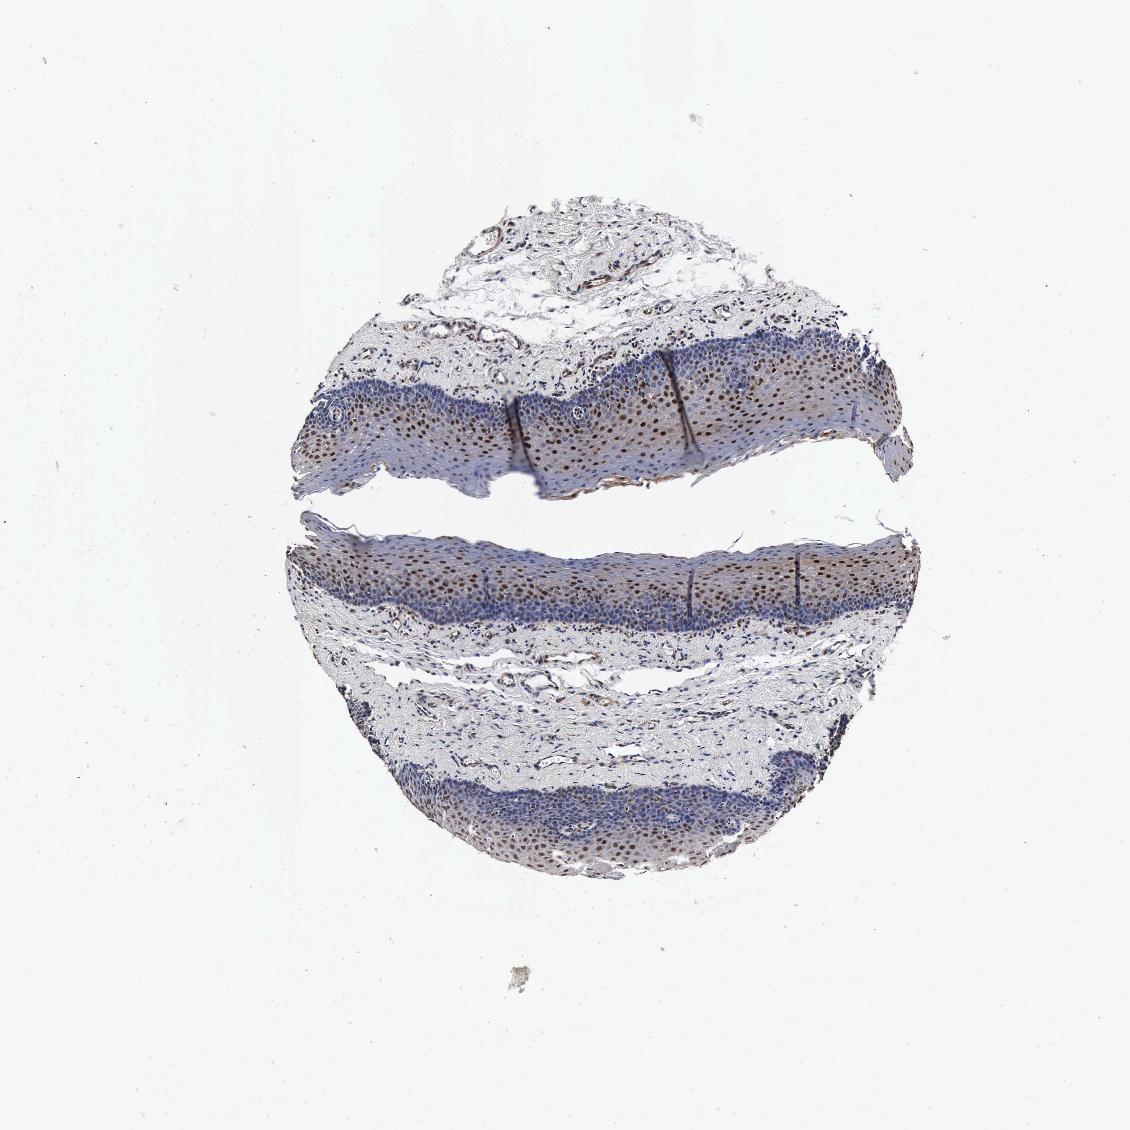

TISSUE PRIMARY DATA ORAL MUCOSA Show tissue menu

Oral mucosa

ORAL MUCOSA - Antibody stainingi

Antibody staining in the annotated cell types in the current human tissue is reported as not detected, low, medium, or high, based on conventional immunohistochemistry profiling in selected tissues. This score is based on the combination of the staining intensity and fraction of stained cells.

Each image is clickable and will lead to virtual microscopy that enables deeper exploration of all samples and also displays staining intensity scores, fraction scores and subcellular localization as well as patient and tissue information for each sample.

Antibody HPA041344Antibody HPA049132Antibody CAB000362Antibody CAB005419

Squamous epithelial cells HighHighMediumMedium